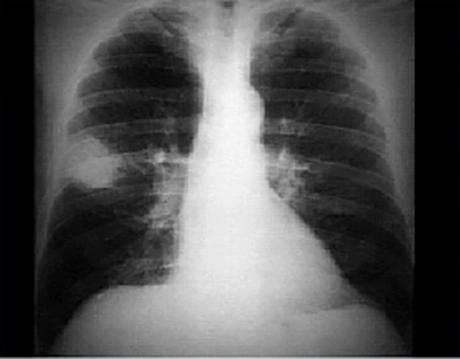

You are incorrect - the best interpretation of the chest X ray in our patient is pulmonary edema with a normal heart size.

In this PA view, there is a peripheral 6 x 4.5 cm radiodensity or infiltrate in right upper lobe. The infiltrate is free of any contained calcification or stranding into the adjacent pulmonary parenchyma. Atelectasis and signs of hilar adenopathy are also absent. The cardiac silhouette, pulmonary vasculature and bony structures are normal.